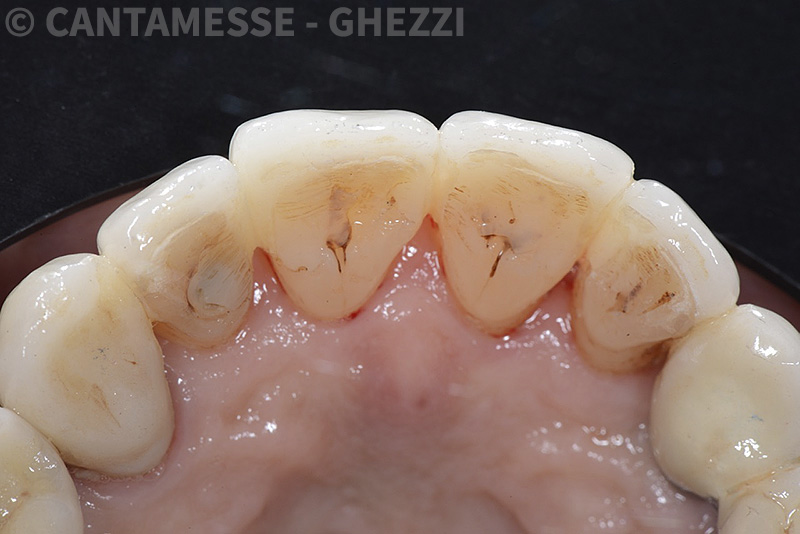

PREMESSA: in seguito all’estrazione dell’incisivo laterale superiore di destra, resasi necessaria per cause batteriche, si decide di affrontare il caso con il posizionamento di un impianto in sostituzione dell’elemento mancante dopo guarigione del sito infetto. Con tecniche rigenerative sia dei tessuti ossei mancanti a causa dell’infezione pregressa, sia dei tessuti gengivali che appaiono inizialmente troppo spostati in alto, si ripristina una corretta morfologia delle parabole (contorni) gengivali e delle papille interdentali (triangoli di gengiva tra due denti vicini).

Vengono utilizzati 2 tipi di provvisori: il primo, cementato ai denti vicini, viene utilizzato dal momento dell’estrazione del dente fino ad impianto osteointegrato (circa 6 mesi); il secondo, avvitato direttamente all’impianto, ha una funzione di prova estetica ma soprattutto di guida per la maturazione dei tessuti gengivali peri-implantari portandoli verso la maturazione completa prima di posizionare la corona finale in disilicato di litio.